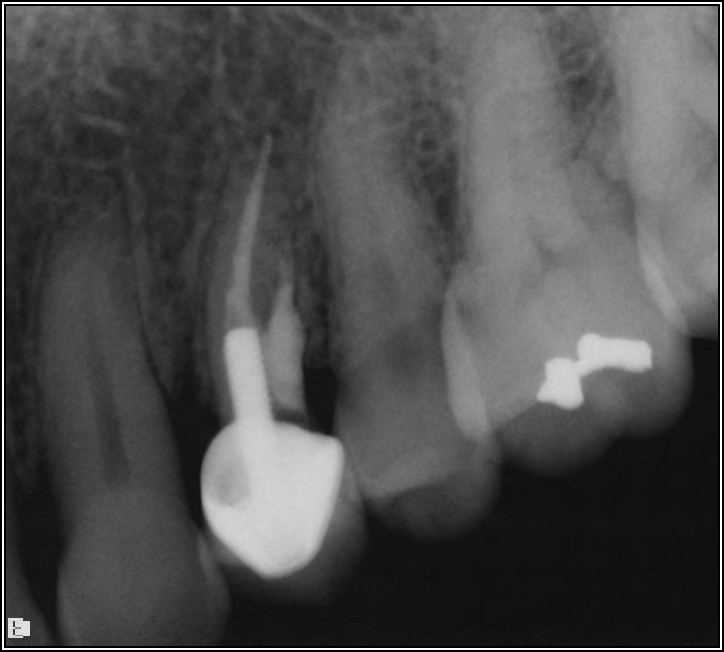

The rules for placement of a post depend on good retention: the greater the length, the greater the retention.3 Also, two-thirds of the length of the root is ideal, but 4 to 5 mm of apical gutta-percha is essential because anything less than that will disrupt the seal.8 Figure 14 shows a case where a patient had a post, core, and crown. The threaded post was shorter than ideal because the tooth was longer. Not visible was the mental foramen underneath. The patient did not have the financial resources to have the case redone. However, when the post would be removed, the clinician would need to trephine or use an ultrasonic around it, making the access bigger than an ideal conservative access. Potentially, the crown would come off. The patient did not have finances for re-treating the tooth and could not have an apicoectomy because the mental foramen was directly under the tooth.

The options, therefore, were to extract it and put a bridge or an implant in later when funds were acquired, or, as was done in this case, perform an intentional replant. The clinician extracted the tooth, cut it, placed MTA, and then put it back under occlusion using sutures—although the clinician would normally put composite in each corner to maintain it and would not etch. Usually after 2 weeks, there is stability. Figure 15 shows the postoperative radiograph, and Figure 16 shows a radiograph 4.5 years later. The patient's probing went from 3 to 4 mm, but overall it was a success because something is always lost coronally, whether the case is a replant or an implant.

Fig 15. Postoperative radiograph.

Figure 15

Fig 16. Radiograph after 4.5 years.

Figure 16